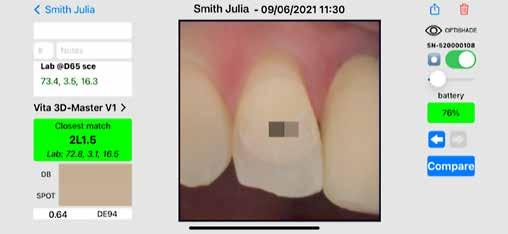

A színtudomány hatalmas komplexitásában magában foglalja többek között a fizikát, a matematikát, a geometriát, a mérést, az érzékelést, a kémiát, az optikát, a művészetet és az emberi pszichológiát. Dióhéjban a színtudomány a pszichofizika. A fogászati szakirodalomban gyakran találkozhatunk félreértelmezett színtudományi fogalmakkal és azok helytelen alkalmazásával. A fogászati területre vonatkozó összetett színtudományi fogalmakat gyakran nehéz könnyen érthető szavakkal elmagyarázni. A következő oldalakon megpróbálunk néhány ilyen fogalmat könnyebben érthető nyelvre lefordítani.

1067 Budapest Podmaniczky u. 39. Tel.: +36 1 311 65 84 www.drvolomdental.hu Straumann GmbH